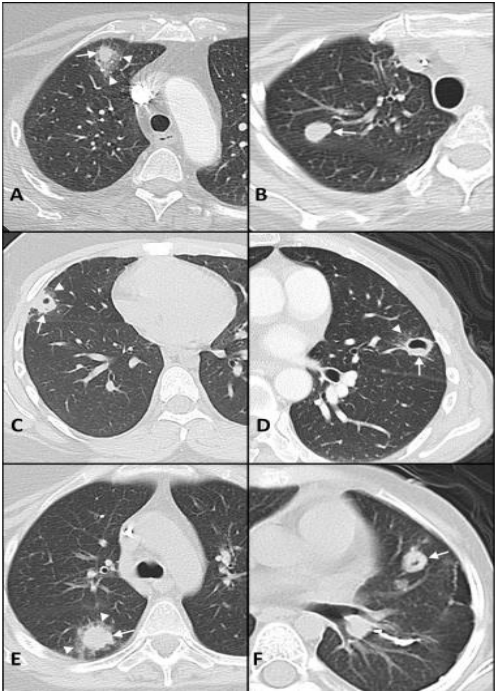

军团菌肺炎的影像学表现不具有特异性,实变是其常见的影像学发现,相对特异性的表现为磨玻璃影中混杂着边缘相对清晰的实变影,各个肺叶均可受累,1/3的病例可合并胸腔积液。免疫抑制患者的影像学表现同样不具有特异性。前述研究回顾性复习了某一癌症中心确诊的40例军团菌肺炎病例,其中,8例表现为单发或多发结节【6例实性伴有磨玻璃晕征或空洞,2例实性结节,边界清楚,没有磨玻璃晕或空洞;6例为1~2个大结节,1例双侧随机分布的大量小结节,1例局灶性磨玻璃影伴微小结节。所有CT均显示结节性浸润,仅有4例(50%)在胸部X线检查中显示结节性浸润】,32例表现为混合性非结节性肺异常(包括肺叶实变、磨玻璃影、斑片状浸润),2例发现肺炎旁胸腔积液。下图A为70岁女性,右肺上叶实性结节伴磨玻璃晕;B为41岁女性,右上肺叶有实心结节;C为17岁男性,右中叶结节伴中央空洞,伴磨玻璃晕;D为51岁女性,舌叶结节,中心空洞,周围磨玻璃晕;E为35岁女性,右下肺叶结节和周围的磨玻璃晕;F为7岁女性,舌叶结节,中央有空洞。也有一些患者偶然发现结节状军团菌肺部感染,症状不明显。我科确诊的一例军团菌肺炎患者,男性,66岁,“咳嗽咳痰伴发热2周”,每日游泳,可能与污染水接触有关,影像学以渗出样改变为主。治疗过程中出现实变、多发结节样改变。军团病的诊断需要借助于有效的检测手段。常用的检测方法包括常规培养、尿抗原检测、核酸检测。培养仍然是诊断军团菌肺炎的“金标准”,但该方法具有滞后性,可能会延误诊断。尿抗原是作为一线的诊断测试,能够快速诊断,使患者得到及时治疗。但尿抗原仅能检出嗜肺军团菌1组菌株,敏感性只有75%,容易导致部分患者被漏诊。核酸检测费用比较高,敏感性高达90%。二代测序能为诊断提供更有效、更快捷的手段。1988年,Cunha教授率先提出了WUH评分系统:①体温>39.4℃;②CRP>187 mg/L;③PLT<171×109/L(如正常下限为125×109/L,则建议PLT<200×109/L);④Na<133 ldh="">225 U/L(339 U/L);⑥干咳(包括不咳嗽、少痰,多痰排除)。【注:每项1分,3分可能诊断,4分可能极大,5分以上确诊】